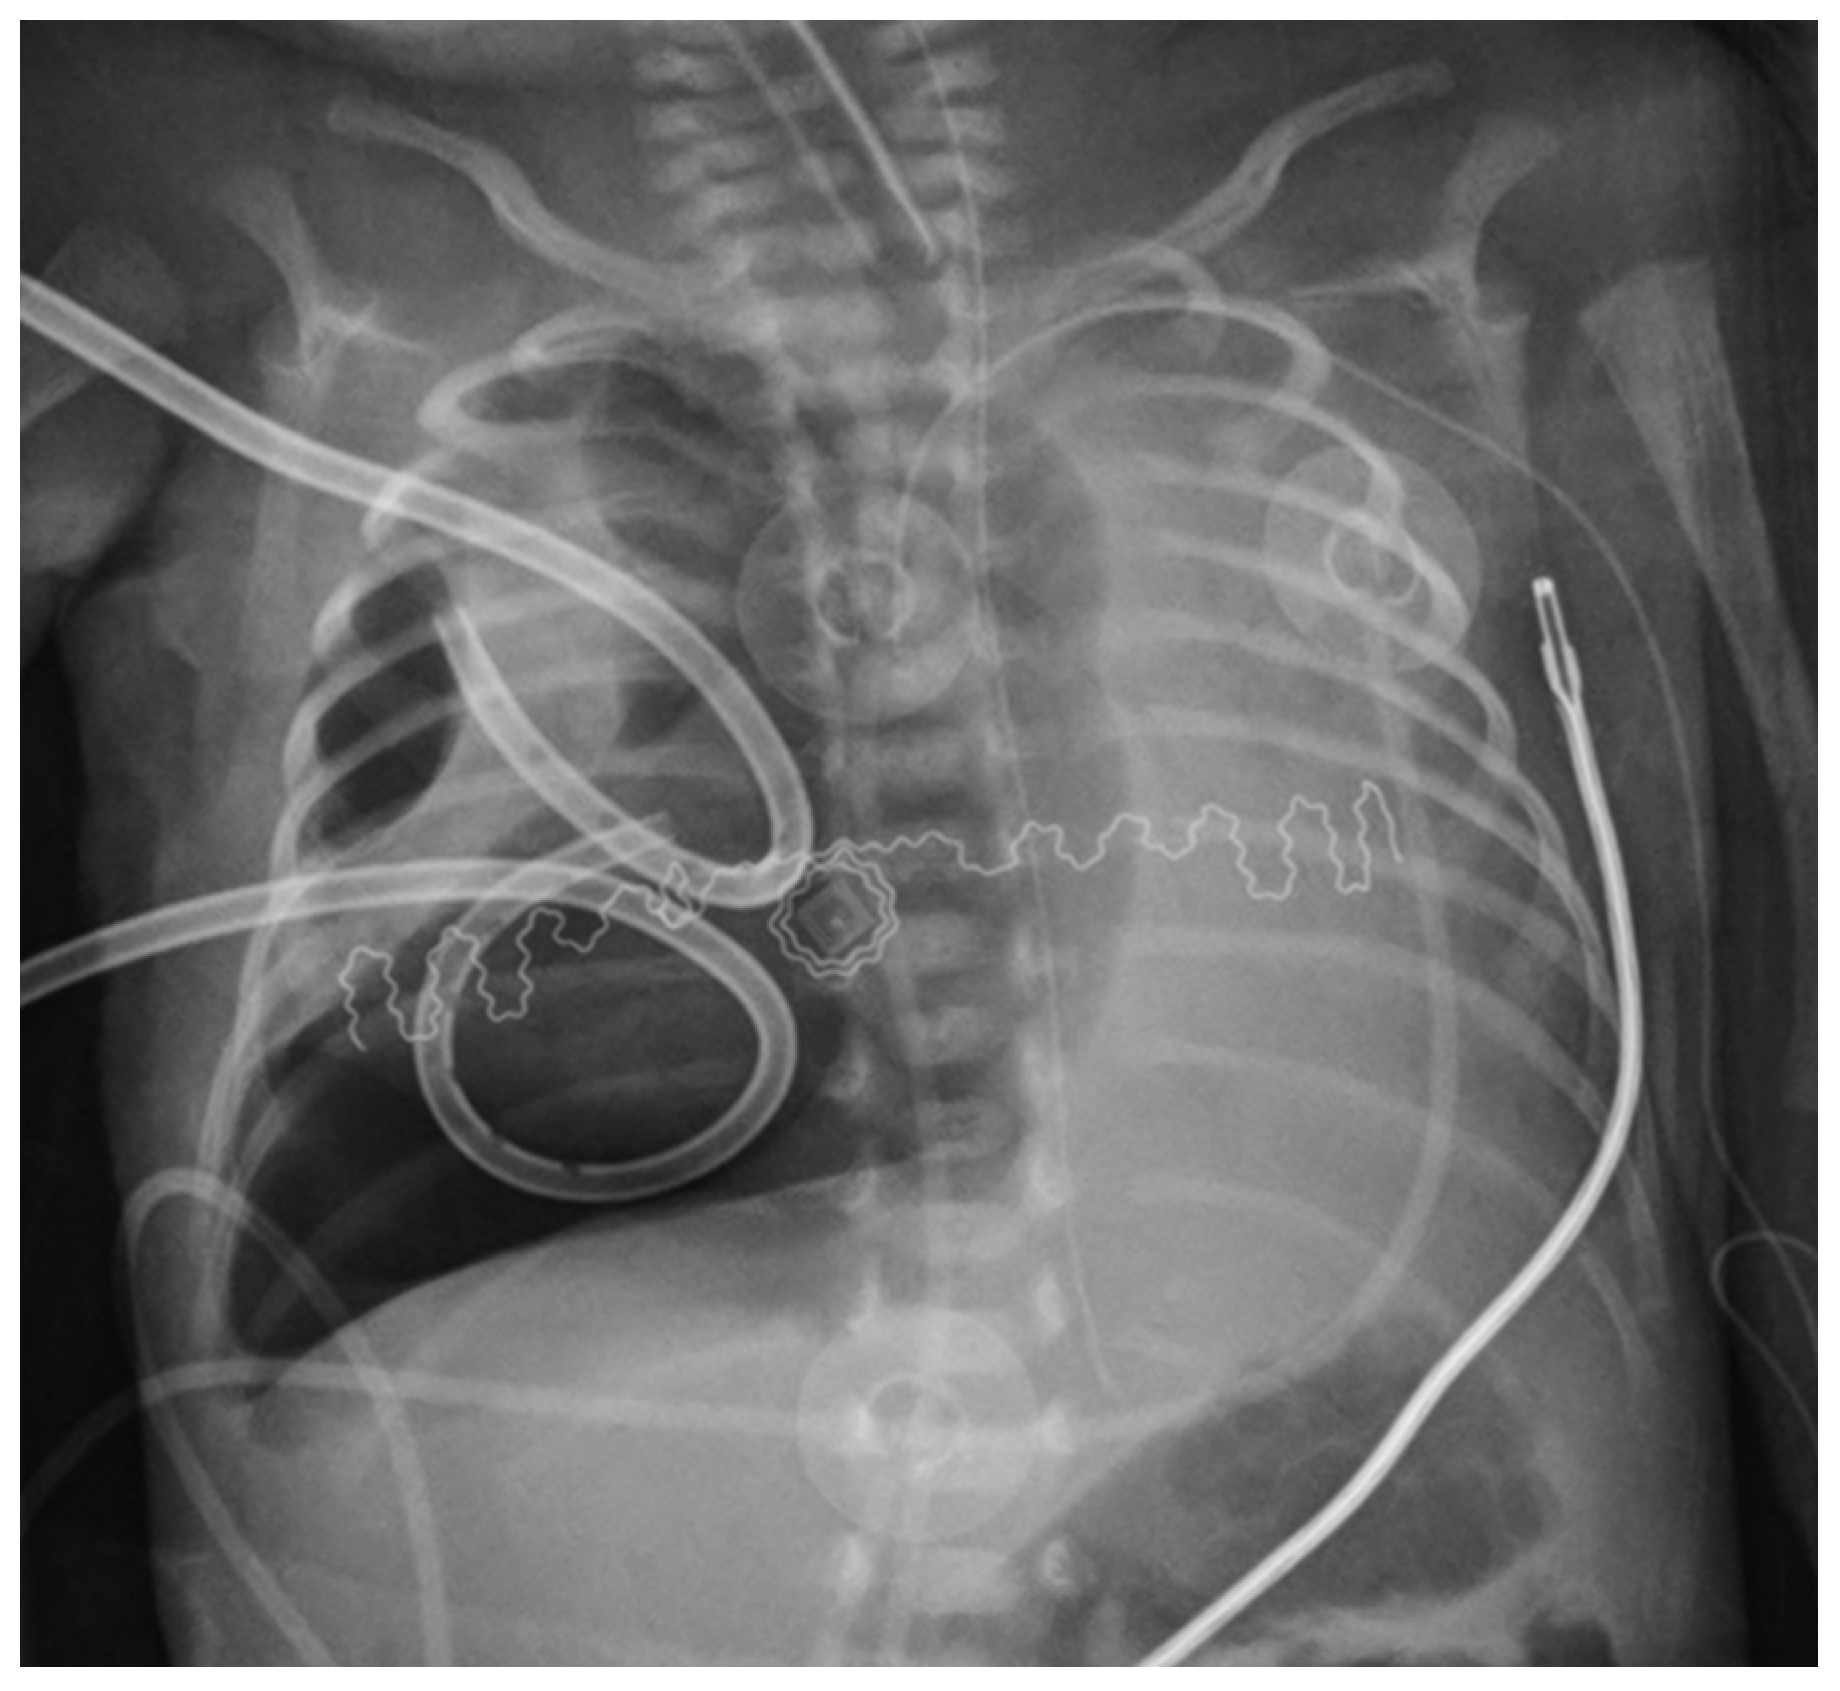

| Present study | 27 | 600 | PTX | Right | Chest drainage and postural therapy | Yes | Fogarty’s catheter 3 FR, inflated 0.2 mL | Direct laryngoscopy | Inflated 1 h/deflated 2 h | 72 h |